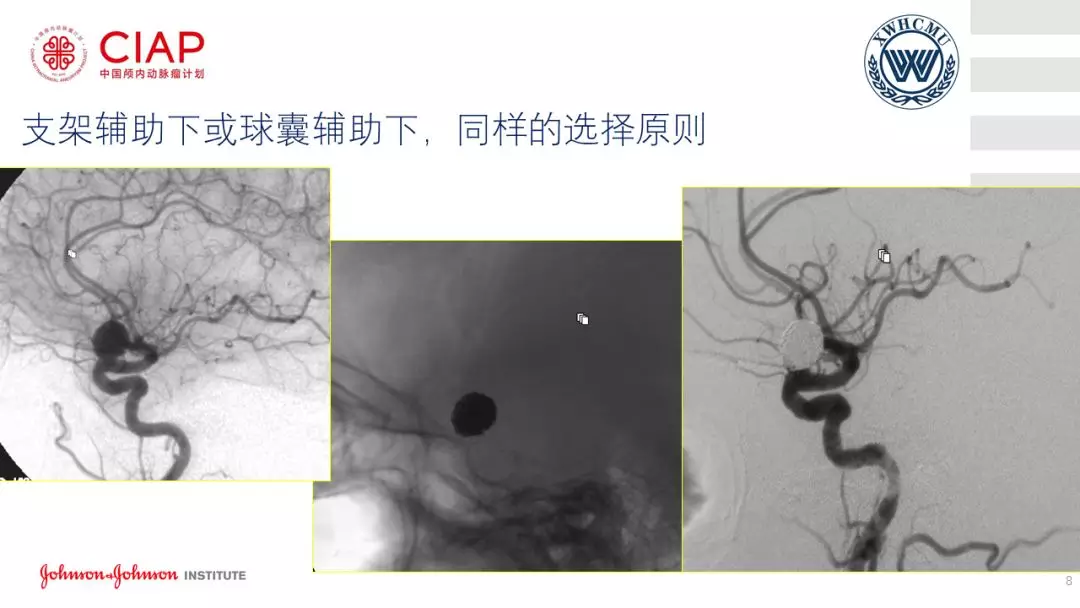

张鹏教授:不同辅助方法下栓塞动脉瘤弹簧圈的选择